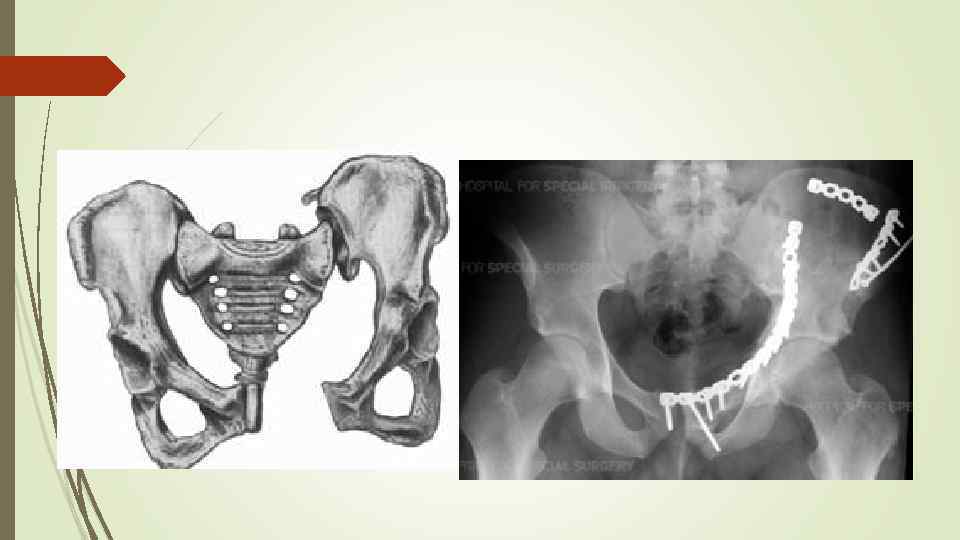

Перелом таза

Принципы укладки в зависимости от месторасположения перелома 1. При разрыве лонного сочленения и переднего полукольца – больной укладывается в гамак, подвешенный за Балканскую раму

2. Без расхождения лонных и лобковых костей – больной укладывается на щит, ноги согнуты и отведены, под колени валик.

3. При переломах крестцово-подвздошного сочленения со смещением половины таза и дна вертлужной впадины производят скелетное вытяжение за мыщелки бедра с грузом 6 -8 кг.